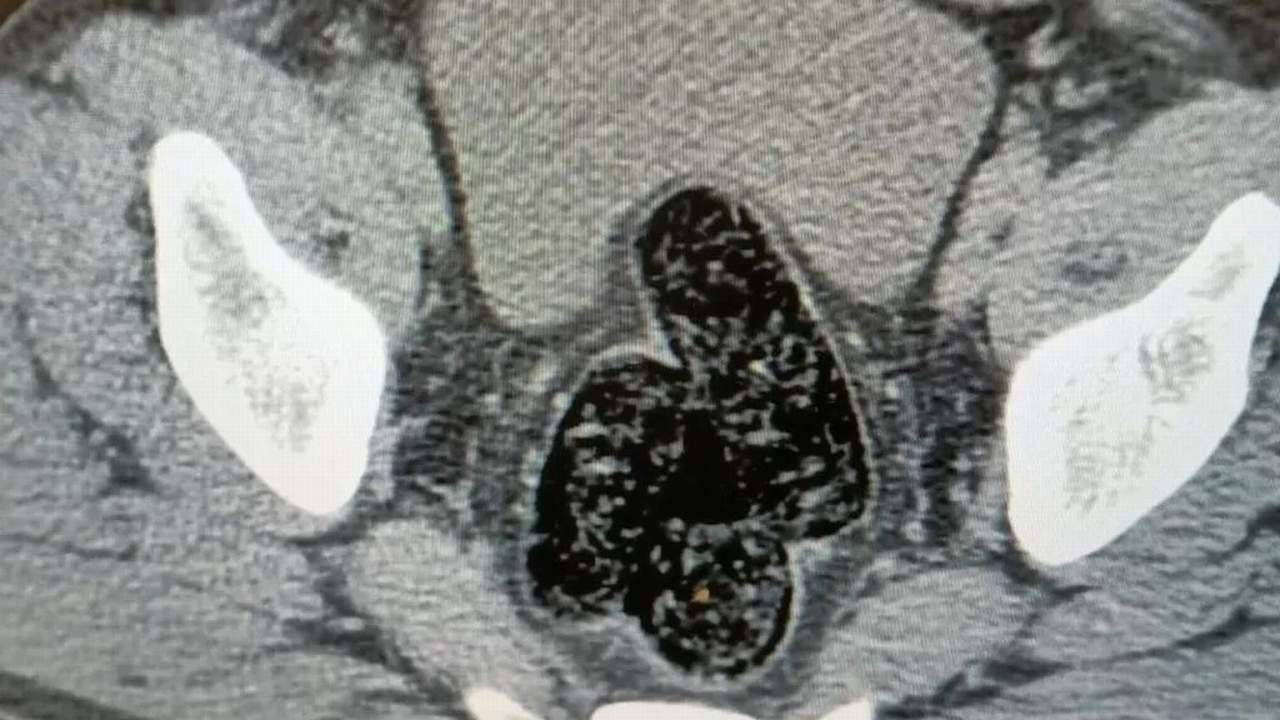

Şahsın devam eden işlemlerinde gözlerindeki kızarıklık, yemek ihtiyacı istememesi, aşırı tedirgin davranışlar sergilemesi üzerine yapılan iç beden muayenesi neticesinde röntgen vasıtasıyla makat ve bağırsak kısmında uyuşturucu kapsülleri olduğu tespit edildi. Doğal yöntemlerle şahıstan 12 adet kapsül toplam daralı ağırlığı 345.19 gram gelen metamfetamin ele geçirildi. Şahsın üzerinden ve iç bedeninden toplamda 355.36 gram uyuşturucu madde ele geçirildi.